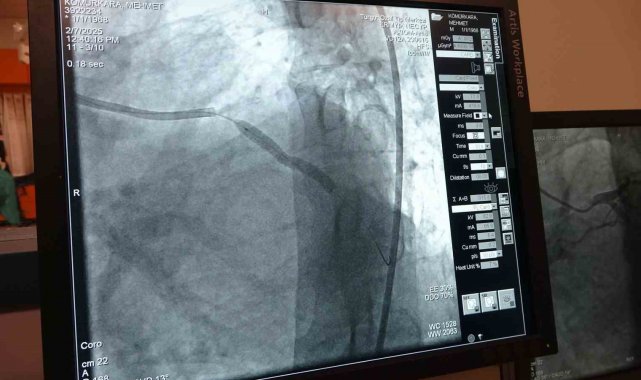

Pakdemir, "Bazen kalbin bir damarında 2 damarında ortaya çıkabilir damarın tıkandığı bölgenin altında beslenemeyen yerlere vücut ince küçük damarlar geliştirebilir biz buna kollateral damarlar diyoruz normalde istirahatle hemen gezse bile hastaya günlük aktivitesinin bize ya da bir efor sarf ettiğinde bunlar yetmez. Bu durum yeterli olmayınca bazen şikayetlere yol açar en büyük şikayetlerinin işte eforla gelen nefes darlığı çarpıntı göğüs ağrısı bazen öyle bir hale gelir damarlar tam oluşmadığı zaman tam gelişmediği zaman dinlenme dahi günlük aktivitelerini yaparken dahi hatta göğüs ağrısı ve nefes darlığı şikayeti olur. Kronik total oklüzyon (CTO)dediğimiz damarlar genellikle her anjio olan her 5 hastadan birinde bulunur yaşla yaşlılıkla giderek sıklığı artar yani 65 yaşının üstünde yüzde 40'larda iken yetmişli 80 yaşları geçtiğimiz zaman bu oran yüzde 40- 45'e kadar yükselir. Damarın içerisindeki darlığın yapısı doğası çok sert bir yapı olduğu için anjio ile girdiğimizde daha değişik geliştirilmiş kompleks malzemelerle ve değişik tekniklerle açmak zorunda kalıyoruz. Normalde hastanın iki kasığını kullanarak 2 kateteri yerleştiriyoruz ve sert kesici teller mikro kateterler ona özel geliştirilmiş balonlar ve destek kateterleriyle bir taraftan tıkalı damara müdahale ederken bir taraftan da alt tarafının görüntülenmesini sağlıyoruz. Bu işlem deneyimli bir merkezde yapıldığı zaman dünya çapında yüzde 70 başarısı vardır. Klinik olarak Türkiye'de bu işi en iyi yapan merkezlerden biriyiz" diye konuştu